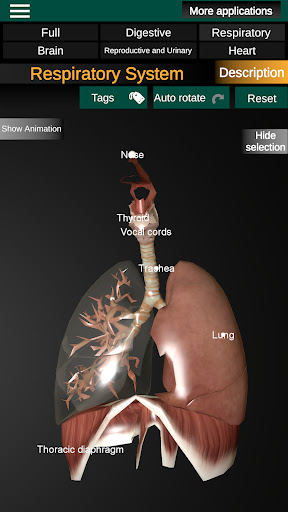

* Ademhalingssysteem, inclusief de luchtpijp, bronchiën, longen en een animatie van dit systeem.